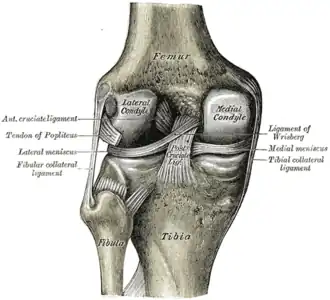

Ligaments

The ligaments surrounding the knee joint offer stability by limiting movements and, together with the menisci and several bursae, protect the articular capsule.[19]

Intracapsular

The knee is stabilized by a pair of cruciate ligaments. These ligaments are both extrasynovial, intracapsular ligaments.[20] The anterior cruciate ligament (ACL) stretches from the lateral condyle of femur to the anterior intercondylar area.[13] The ACL prevents the tibia from being pushed too far anterior relative to the femur.[13] It is often torn during twisting or bending of the knee.[21] The posterior cruciate ligament (PCL) stretches from medial condyle of femur to the posterior intercondylar area. This ligament prevents posterior displacement of the tibia relative to the femur.[13] Injury to this ligament is uncommon but can occur as a direct result of forced trauma to the ligament.

The transverse ligament stretches from the lateral meniscus to the medial meniscus. It passes in front of the menisci. It is divided into several strips in 10% of cases.[10]: 208 The two menisci are attached to each other anteriorly by the ligament.[22] The posterior (of Wrisberg) and anterior meniscofemoral ligaments (of Humphrey) stretch from the posterior horn of the lateral meniscus to the medial femoral condyle. They pass anterior and posterior to the posterior cruciate ligament respectively.[13][10]: 208 The meniscotibial ligaments (or "coronary") stretches from inferior edges of the menisci to the periphery of the tibial plateaus.

Extracapsular

The patellar ligament connects the patella to the tuberosity of the tibia. It is also occasionally called the patellar tendon because there is no definite separation between the quadriceps tendon (which surrounds the patella) and the area connecting the patella to the tibia.[23] This very strong ligament helps give the patella its mechanical leverage[24] and also functions as a cap for the condyles of the femur. Laterally and medially to the patellar ligament, the lateral and medial retinacula connect fibers from the vasti lateralis and medialis muscles to the tibia. Some fibers from the iliotibial tract radiate into the lateral retinaculum and the medial retinaculum receives some transverse fibers arising on the medial femoral epicondyle.[10]: 206

The medial collateral ligament (MCL a.k.a. "tibial") stretches from the medial epicondyle of the femur to the medial tibial condyle. It is composed of three groups of fibers, one stretching between the two bones, and two fused with the medial meniscus. The MCL is partly covered by the pes anserinus and the tendon of the semimembranosus passes under it.[10]: 206 It protects the medial side of the knee from being bent open by a stress applied to the lateral side of the knee (a valgus force).[10]: 206

The lateral collateral ligament (LCL a.k.a. "fibular") stretches from the lateral epicondyle of the femur to the head of fibula. It is separate from both the joint capsule and the lateral meniscus.[10]: 206 It protects the lateral side from an inside bending force (a varus force). The anterolateral ligament (ALL) is situated in front of the LCL.

Lastly, there are two ligaments on the dorsal side of the knee. The oblique popliteal ligament is a radiation of the tendon of the semimembranosus on the medial side, from where it is direct laterally and proximally. The arcuate popliteal ligament originates on the apex of the head of the fibula to stretch proximally, crosses the tendon of the popliteus muscle, and passes into the capsule.[10]: 206